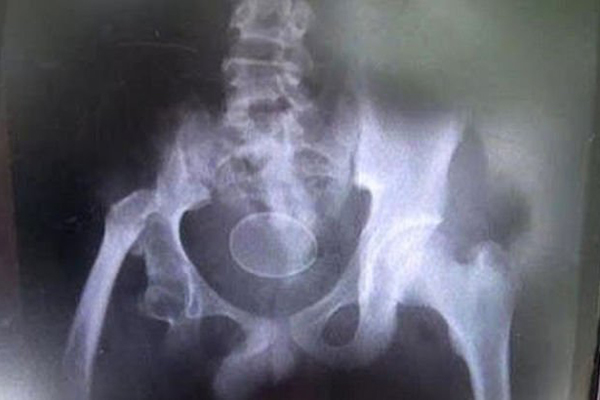

Endonezya'da duyanları hayrete düşüren bir olay yaşandı. İddiaya göre; 14 yaşındaki Akmal adlı çocuk, doktorların gözü önünde yumurtladı.

Daily Mail'de yer alan habere göre; Endonezya'nın Gowa şehrinde yaşayan Akmal, 2016 yılından beri düzenli olarak yumurtladığını açıkladı. Daha önce de defalarca hastaneye kaldırıldığı kaydedilen çocuğun doktorların önünde iki kez yumurtladığı iddia edildi.

Böyle bir şeyin tıbben imkansız olduğunu kaydeden uzmanlar, yumurtaların rektuma kasıtlı olarak sokulduğunu düşünüyor. Fakat çocuk ve babası bu iddiaları yalanladı.

Baba Rusli şunları söyledi: "İki yıl içinde 18 kez yumurtladı, şimdi de iki tane... İlk yumurtayı kırdığımda içeriğinin sadece sarı olduğunu, yumurtada beyaz olmadığını gördüm" dedi.

İnanması güç olan bu olay karşısında doktorlar yaşanılan bu durumu araştıracağını duyurdu.